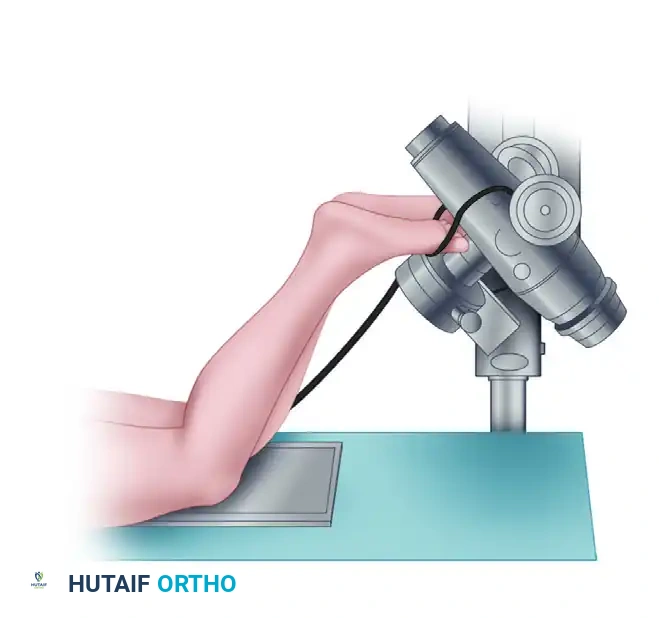

Standard and Specialized Positioning Techniques

Proper patient positioning is paramount for obtaining reproducible and diagnostically accurate radiographs of the patellofemoral joint.

2. Axial View Positioning:

The axial view is critical for assessing the dynamic tracking of the patella within the trochlear groove. The knee is typically flexed to 30 or 45 degrees.

3. Skyline View Positioning:

The skyline view provides a tangential perspective of the patellofemoral articulation, allowing the surgeon to evaluate the medial and lateral facets, the depth of the trochlear sulcus, and the presence of marginal osteophytes.